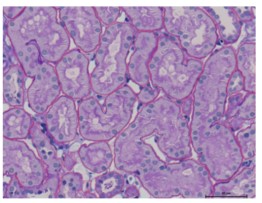

this image shows tubulus and PTC and how they connected

1-Tubulus

The kidneys are essential organs that filter blood, remove waste, and balance fluids. Inside each kidney, there are tiny structures called nephrons, each containing a long, coiled tube known as a tubule. The tubules play a crucial role in filtration, reabsorption, and secretion. They filter waste and excess substances from the blood, reabsorb essential substances like water, glucose, and salts back into the bloodstream, and secrete additional waste products into the fluid that becomes urine. The tubules are composed of several parts: the Proximal Convoluted Tubule (PCT) where most reabsorption occurs, the Loop of Henle which helps concentrate urine, the Distal Convoluted Tubule (DCT) that fine-tunes reabsorption and secretion, and the Collecting Duct where urine is concentrated further before draining into the renal pelvis and then to the bladder. Analyzing kidney tubules is important for assessing kidney function, detecting diseases such as acute tubular necrosis or chronic kidney disease, and monitoring the effectiveness of treatments for kidney conditions. Thus, understanding the function and health of tubules is key to evaluating overall kidney health.

2-Glomerulus

An essential component of every kidney nephron is the glomerulus, which acts as the first site of blood filtration. The glomerulus is a network of microscopic capillaries surrounded by Bowman’s capsule that filters blood by letting bigger molecules like proteins and blood cells stay within while permitting water, salts, glucose, and waste items like urea to flow through its porous membranes. The filtrate created by this filtering process eventually turns into urine when it passes past the nephron. One important measure of kidney health is the glomerular filtration rate (GFR), which expresses how efficiently the glomerulus filters blood. Through processes such as the renin-angiotensin-aldosterone system, the glomerulus also contributes to the regulation Proteinuria and hematuria are indications of diseases that affect the glomerulus, such as glomerulonephritis or diabetic nephropathy. These diseases can compromise filtration. As a result, glomerular health analysis plays a crucial role in the diagnosis and treatment of kidney illnesses. Tests like urinalysis, GFR calculation, and kidney biopsies offer important information on this regard.

3-Peri Tubular Capillaries (PTC)

The kidneys’ network of tiny blood arteries known as the Peritubular Capillaries (PTC) surrounds the renal tubules and is essential to urine production and blood filtration. These capillaries, which emerge from the efferent arteriole, aid in the chemical exchange between the tubular fluid and the blood. They are necessary to ensure that vital materials like water, glucose, amino acids, and electrolytes are not wasted in urine by reabsorbing them back into the circulation. Furthermore, PTCs help to remove waste and excess ions from the blood into the tubular fluid, preserving chemical equilibrium. PTCs’ thin walls facilitate simple material transport and provide for effective exchange due to their near proximity to the tubules. They also provide the essential nutrition and oxygen to the tubule cells. The body’s ability to regulate fluid balance, electrolyte levels, and acid-base balance depends on this effective exchange mechanism. Damage to these capillaries can impede kidney function and result in illnesses. This damage is frequently caused by disorders like diabetes and hypertension. As a result, PTC function analysis is crucial for the diagnosis and treatment of kidney-related disorders, with blood and urine tests offering information on the state of the kidneys and their function in homeostasis.